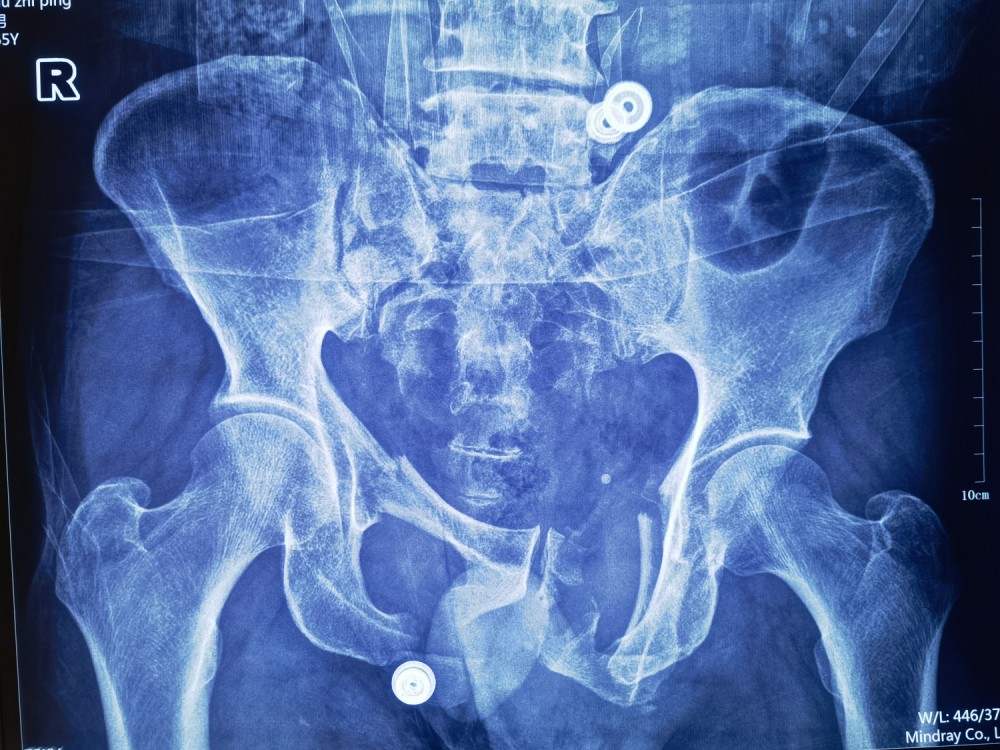

9月2日中午,120急救车送来一名骨盆骨折患者,经91直播 创伤急救中心精确诊断,患者被收治创伤外科中心A区。患者65岁,男性,机场建筑工人,因工程车碾压致伤。当日91直播 值班医生是创伤外科中心A区于成涌副主任医师,他通过详细询问病史及查体,凭借多年的临床经验,推断患者入院后虽然生命体征暂时平稳,但心电监护显示心率加快,血压亦有下降趋势,患者处于休克代偿期,病情随时可能出现恶化。

考虑患者骨盆骨折合并盆腔脏器损伤可能性极高,立刻给予患者补液抗休克并留置导尿,但未见尿液引出,随即联系医技科室开辟绿色通道并护送患者急行腹部CT、彩超、心电图等相关检查,并请普通外科紧急会诊,吕冰副主任医师为患者进行尿道逆行造影,结果显示,尿道断裂、膀胱破裂。正是因为于成涌医师的准确判断以及吕冰医师的专业支持,为接下来的抢救工作赢得了黄金时间。

骨盆X片及CT三维重建